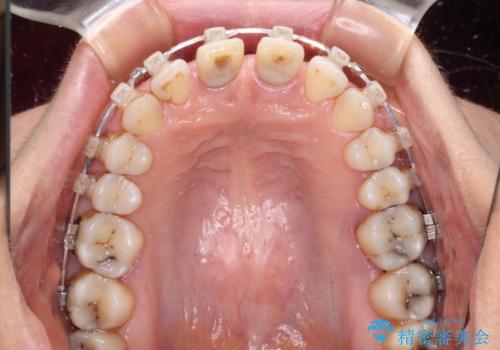

- 隙間の空いた前歯をセラミッククラウンで補隙したところ、歯肉から出血してしまい、何とかしたいとのことで来院された患者様です。

初めは前歯のみの処置で改善を希望されていたため、広範囲に処置範囲を広げることで歯の幅がバランスする治療を提案しましたが、削らなければならない歯が増えてしまうため、患者様と相談して全顎矯正により前歯のスペースを閉じていくこととしました。

不適合なクラウンが装着されていたため、歯周ポケットが深くなっていましたので、矯正治療前に歯周外科処置を行って歯周ポケットを除去し、矯正治療後にオールセラミッククラウンにて補綴治療を行うこととしました。